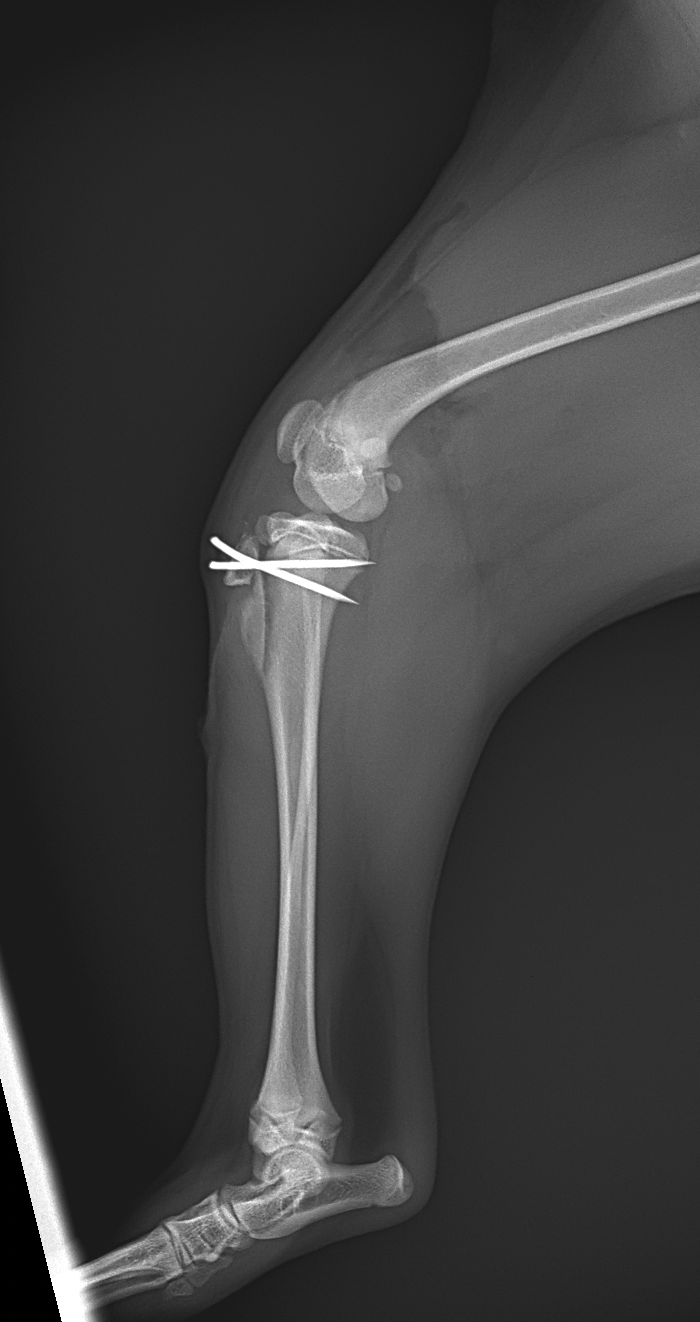

膝蓋骨内方脱臼G4により右後肢の負重が弱いという患者さんが紹介受診されました。膝蓋骨は大腿骨滑車から脱臼したままで大腿骨滑車内に誘導することができませんでした。大腿骨の変形などは幸い確認されませんでした。大腿骨滑車形成術、内側広筋の切離、脛骨粗面外側移行術、外側余剰関節包の切除によりアライメント手術を行いました。これから後療法も重要になります。